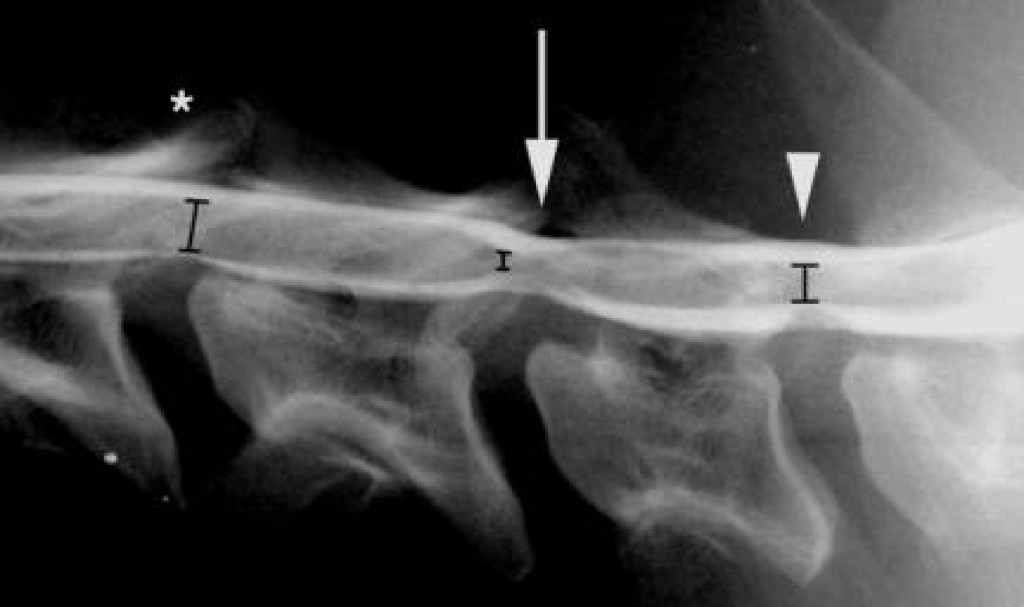

Prechodový stavec

Prechodový stavec je jednou z najčastejších kongenitálnych anomálií chrbtice. Vyznačuje sa anatomickými charakteristikami oboch susedných oddielov chrbtice, a to jednostranne alebo obojstranne. Jeho prítomnosť môže vyústiť v rozdiely v počte stavcov v jednotlivých úsekoch chrbtice. Prechodový stavec sa môže vyskytovať na prakticky ktoromkoľvek spojení medzi 2 úsekmi chrbtice – cervikotorakálnom, thorakolumbálnom, lumbosakrálnom alebo sakrokaudálnom. Najväčšia pozornosť je venovaná výskytu prechodového stavca na lumbosakrálnom spojení (LTV), kde môže spôsobovať najviac klinických problémov.